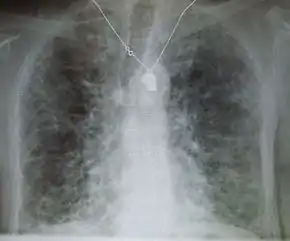

X-ray and CT (radiography and computed tomography)

Chest radiography is usually the first test to detect interstitial lung diseases, but the chest radiograph can be normal in up to 10% of patients, especially early in the disease process.[13][14]

High-resolution CT of the chest is the preferred modality and differs from routine CT of the chest. Conventional (regular) CT chest examines 7–10 mm slices obtained at 10 mm intervals; high resolution CT examines 1–1.5 mm slices at 10 mm intervals using a high-spatial-frequency reconstruction algorithm. The HRCT therefore provides approximately 10 times more resolution than the conventional CT chest, allowing the HRCT to elicit details that cannot otherwise be visualized.[13][15]

Radiologic appearance alone, however, is not adequate and should be interpreted in the clinical context, keeping in mind the temporal profile of the disease process.[13]